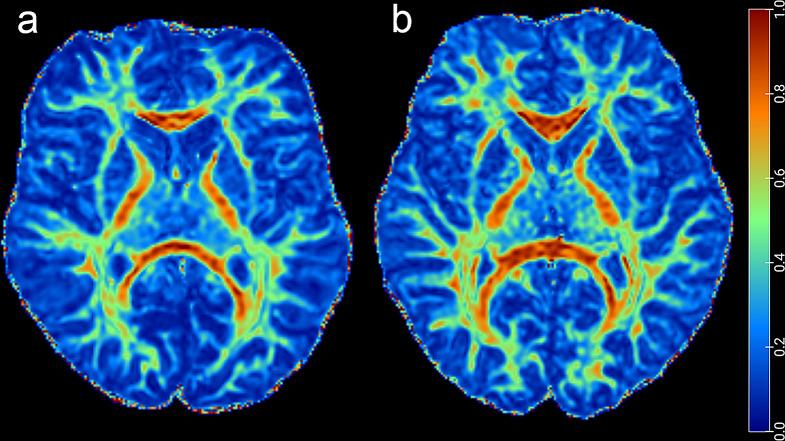

Spinal muscular atrophy (SMA) is caused by reduced expression of survival motor neuron (SMN) protein. Previous studies indicated SMA causes not only lower motor neuron degeneration but also extensive brain involvement. This study aimed to investigate the changes of brain white matter and structural network using diffusion tensor imaging (DTI) in children with type 2 and 3 SMA.

Forty-two type 2 and 3 pediatric SMA patients and 42 age- and gender-matched healthy controls (HC) were prospectively enrolled in this study. The tract-based spatial statistics (TBSS) was used to assess white matter integrity and the structural network properties were calculated based on DTI white matter fiber tracking and the graph theory approach. A partial correlation was performed to explore the relationship between white matter parameters and clinical characteristics.

In total, 42 patients (mean age, 10.86 ± 4.07 years; 23 men) were included. TBSS analysis revealed widespread white matter changes in SMA patients. The SMA patients showed changes in multiple small-world and network efficiency parameters. Compared to the HC group, SMA showed increased characteristic path length (L), normalized clustering coefficient (γ), small-world characteristic (σ), and decreased global efficiency (E) (all p < 0.05). In the node properties, right supramarginal gyrus, right orbital part of superior frontal gyrus, right supplementary motor area, and left median cingulate and paracingulate gyri changed in SMA patients. A decreased axial diffusivity (AD) value was associated with lower Hammersmith Functional Motor Scale-Expanded scores (r = 0.45, p = 0.02), which means that the symptoms of SMA patients are more severe.

This study found white matter and DTI-based brain network abnormalities in SMA patients, suggesting SMN protein deficiency may affect white matter development.